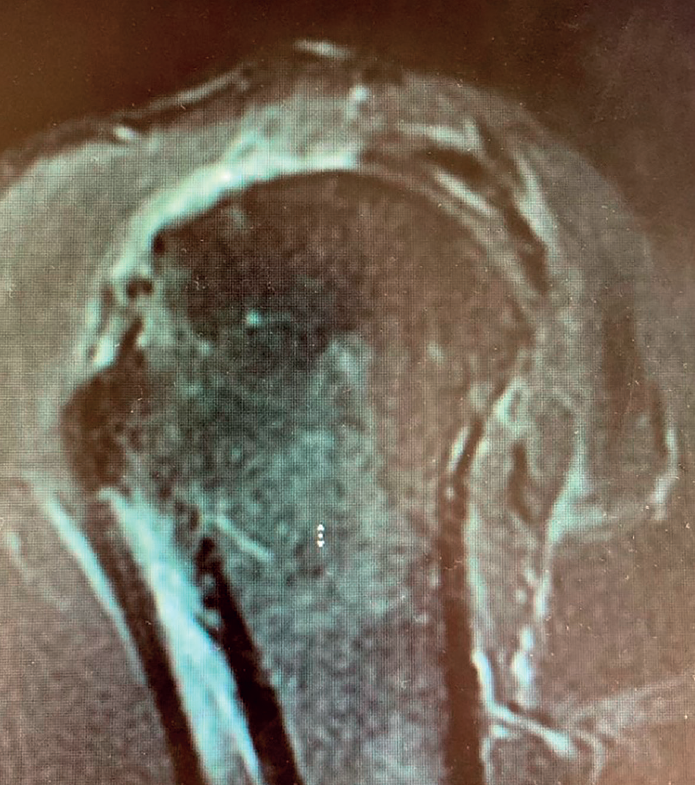

A more controversial issue is its indication in patients with massive cuff rupture in the absence of arthropathy, since it implies performing joint replacement of a joint without osteoarthrosis. In these cases, reverse shoulder replacement has been shown to be an effective alternative that affords predictable pain relief and improved function(15,17)(Figures 1 to 5).

Reverse shoulder replacement shifts the center of rotation distal and medial (Figure 5), increasing the lever arm of the deltoid muscle and recruiting more anterior and posterior fibers of the muscle, improving its function in patients without rotator cuff(1,19,20). In general, the patients can be expected to show increased anterior flexion and abduction of the shoulder. Having greater or lesser external rotation will depend on the quality of the teres minor and infraspinatus, among other factors (Figure 4). With regard to internal rotation in patients with reverse shoulder replacement after massive rupture, the results are less predictable and are conditioned by the implant design and the characteristics of the patient, among other factors. We must know the functional limitations of the implant and inform our patients about the results that can be expected.